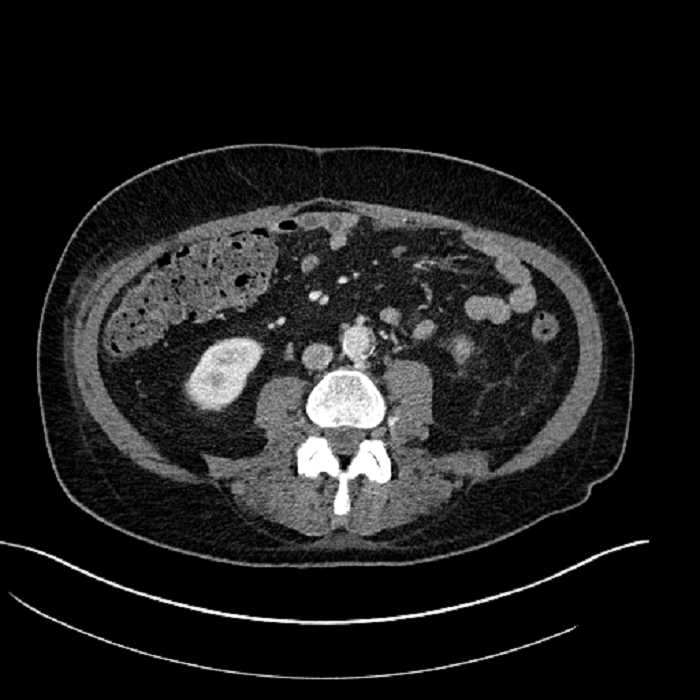

• Mild mural thickening of a segment of the sigmoid colon with adjacent fat stranding and a 1.5 cm fluid and gas collection along the tip of an inflamed diverticulum

• Loss of the normal fat plane between this collection and adjacent loops of small bowel, which demonstrate mural thickening

• No bowel obstruction

Acute sigmoid diverticulitis complicated by a small contained perforation and a large abscess in the right hepatic lobe. Additional small subcapsular abscesses along the anterior margin of the left hepatic lobe.

Additionally, loss of the normal fat plane between the peridiverticular collection and adjacent thickened loops of small bowel raises the potential for an enterocolonic fistula.

Hepatic abscess showing the double target sign with low density internally surrounded by a thin inner enhancing rim (red arrow) and ill-defined outer low density rim (yellow arrow). Blue arrow indicates an internal septation. Red arrows: additional smaller subcapsular abscesses. Red arrow: focal contained perforation associated with diverticulitis.